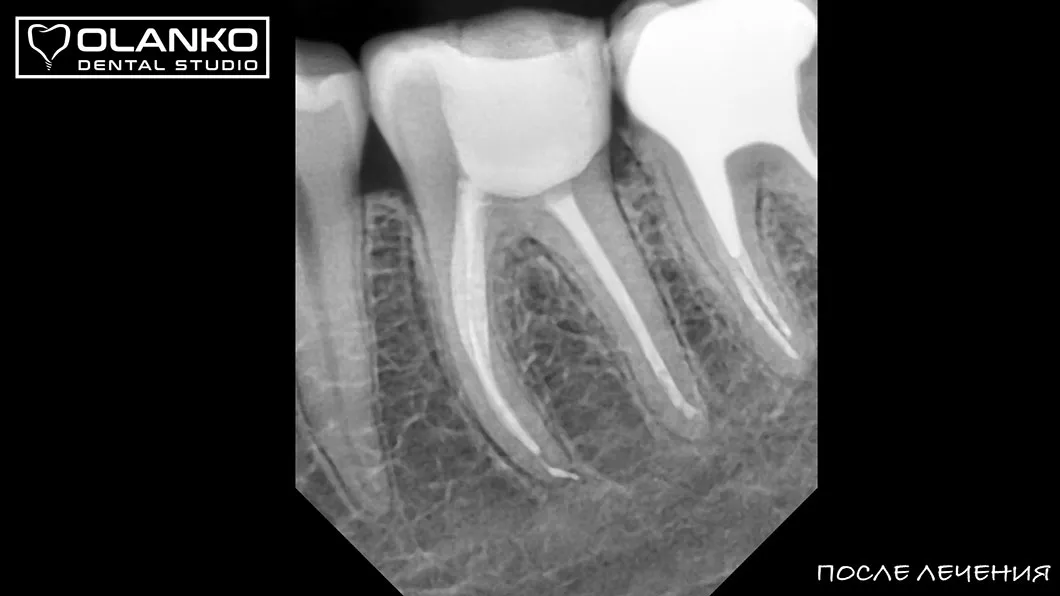

Лечение корневых каналов зуба с использованием микроскопа, на сегодняшний день, является золотым стандартом мировой стоматологической практики. Сложная система корневых каналов в зубе имеет очень малый диаметр и индивидуальную анатомию, поэтому врач, работающий без увеличения, не может качественно очистить и найти все корневые каналы на ощупь.

На примере перелечивания корневых каналов верхнего жевательного зуба

Для лечения простых клинических случаев, как правило, требуется всего один визит длительностью 1,5-2,5 часа.

Сложные случаи перелечивания корневых каналов, искревлённых каналов со сложной анатомией, требуют 2-3 визитов.

Мы имеем огромный клинический опыт лечения зубов со сложной анатомией (искривлёнными, склерозированными каналами), а также повторного перелечивания каналов с кистами, гранулемами, сломанными инструментами, с последующими отличными результатами заживления очагов хронического воспаления.